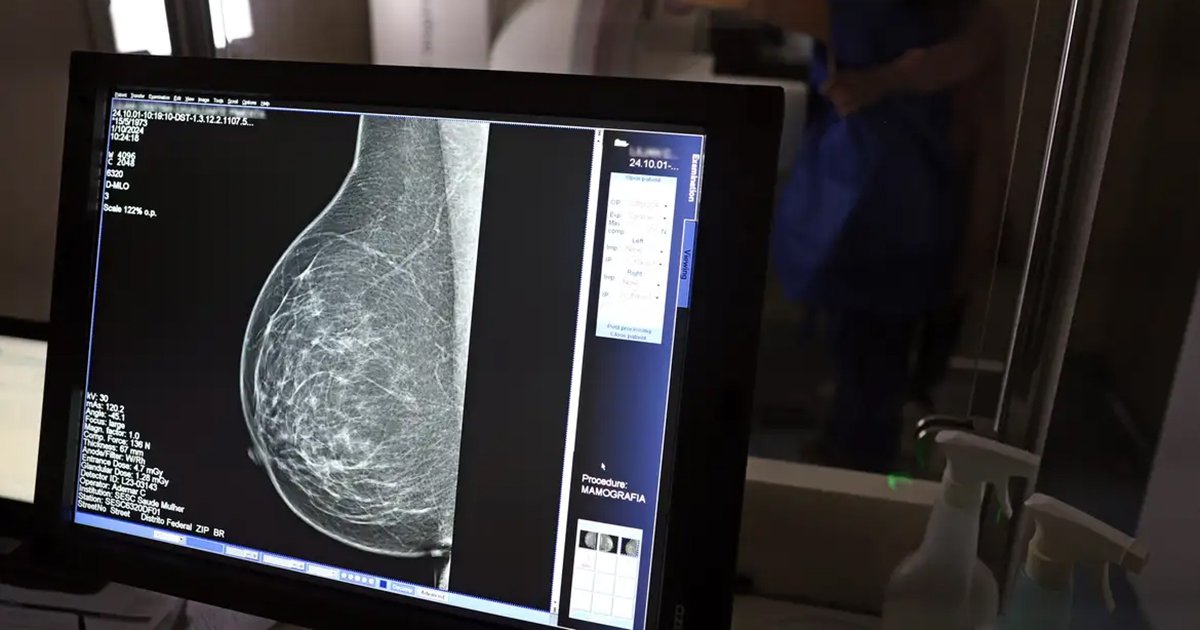

A oferta de mamografia em Tubarão será ampliada durante a campanha do Março Lilás. A iniciativa da Prefeitura busca facilitar o acesso ao exame de rotina e reforçar a importância do diagnóstico precoce do câncer de mama, o tipo mais comum entre as mulheres no Brasil.

O câncer de mama apresenta maiores chances de cura quando identificado nas fases iniciais, principalmente por meio da mamografia regular.